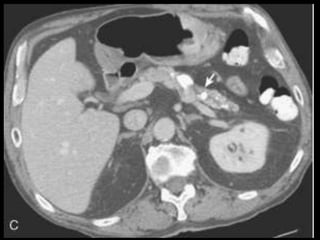

Pseudocistos

Coleções encapsuladas e uniloculadas de líquido

pancreático e material necrosado e proteináceo;

São necessárias 4 semanas ou mais para que um

pseudocisto evolua de uma coleção líquida aguda;

Mais comumente peripancreáticos, mas podem ser

observados no mediastino e na pelve;

Importância do contraste oral positivo;

Metade dos pseudocistos regride

espontaneamente;

Sintomas dependem

Pseudocistos-TC

Coleção líquida redonda ou oval, com uma parede

fina ou espessa, que apresenta intensificação pelo

contraste;

RM: lesão uniloculada bem definida, hipointensa

em T1 e hiperintensa em T2;

Bolhas de gás: infecção, fístula ou à cistostomia

interna;

Hemorragia aguda dentro do cisto: hiperdensa

Estenose ou oclusão venosa, com formação de

varizes ou pseudoaneurismas.